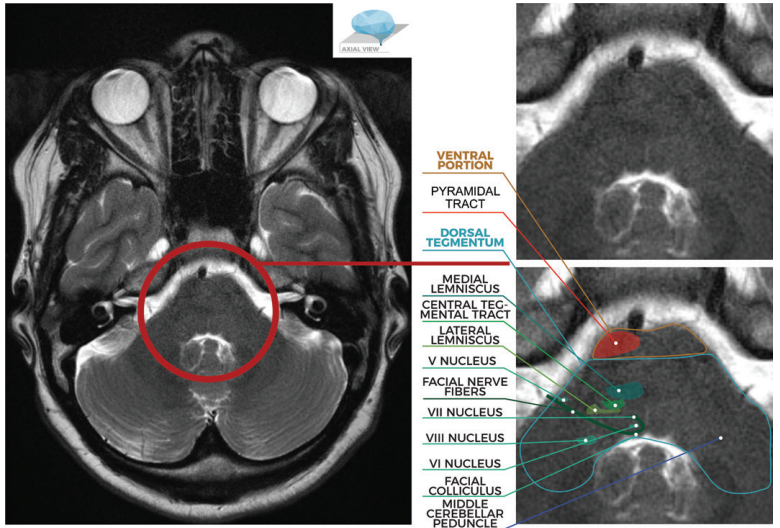

图文并茂:一文掌握脑桥解剖结构及常见综合征

图片尺寸780x528